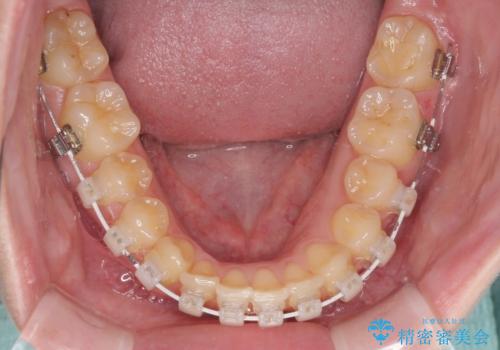

- 矯正装置

- 審美装置

- 治療期間

- 1年6ヶ月